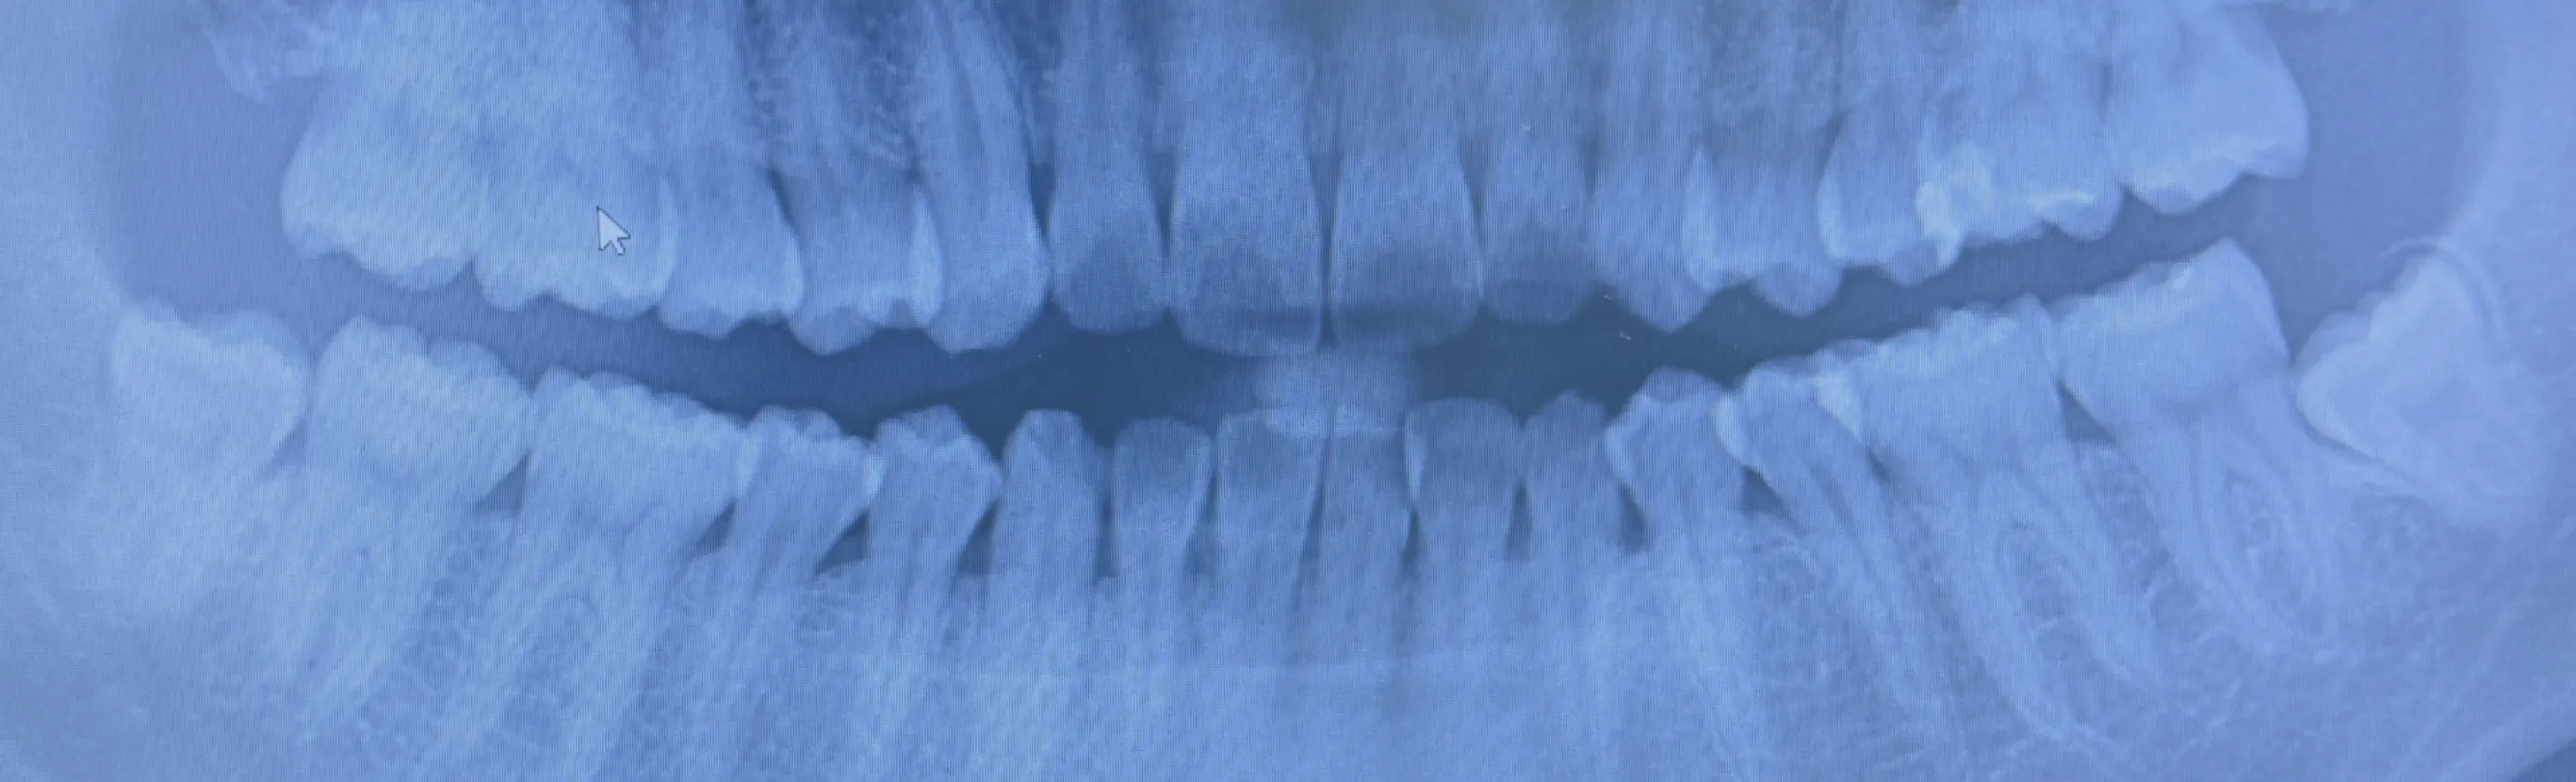

入れ歯治療とは?

入れ歯(義歯)は保険内で装着できるものから、噛む機能や審美性によって保険外(自由診療)の部分・総入れ歯まで様々あります。

BPS 生体機能的超精密義歯

当院は「BPS生体機能的超精密義歯」の認定クリニックで研修機関です。

徹底したエビデンスにもとづいた診断、システム、器具、治療法を行い、「よく噛める・外れない・痛くない・美しい」世界最高水準の生体調和・機能性がとれた義歯の作成を可能にしています。